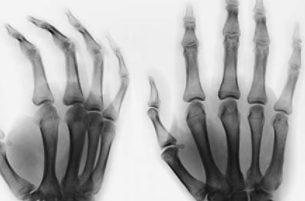

类风湿用什么药,你必须在检查的基础上跟医生直接交流才能确定。而且确定治疗方案是需要一个过程的,因为很多药物发生药效需要一个代谢周期,不可能药到症状就消失。如果代谢周期过了还没起效,才能宣布选择的治疗方案失败,需要尝试新的治疗方案。郑州类风湿医院介绍类风湿这个病个体差异非常大,每个人耐药的情况也不一样。